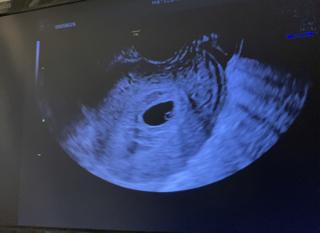

初受診。最終生理から数えて6w2dでした。排卵が遅かったのか、少し小さめで1cm程の胎嚢が見えました。不鮮明で不安でしたが、この後ちゃんと育ってくれました。